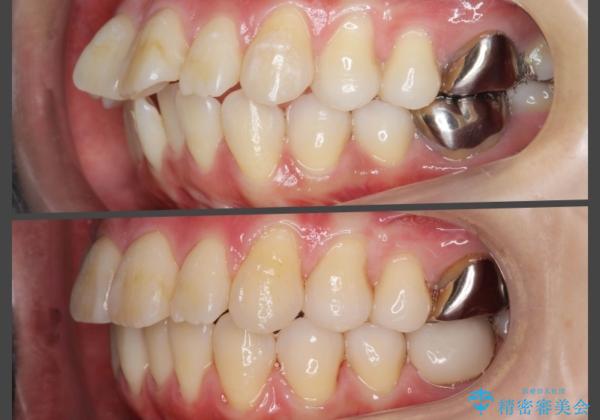

捻れた奥歯 突き出た前歯を治したい

- 出っ歯に見える前歯、捻れてしまった小臼歯の改善を求めて来院されました。

時間はかかりましたが、捻れ、かみ合わせ、前歯の角度の改善が達成され満足いただくことができました。